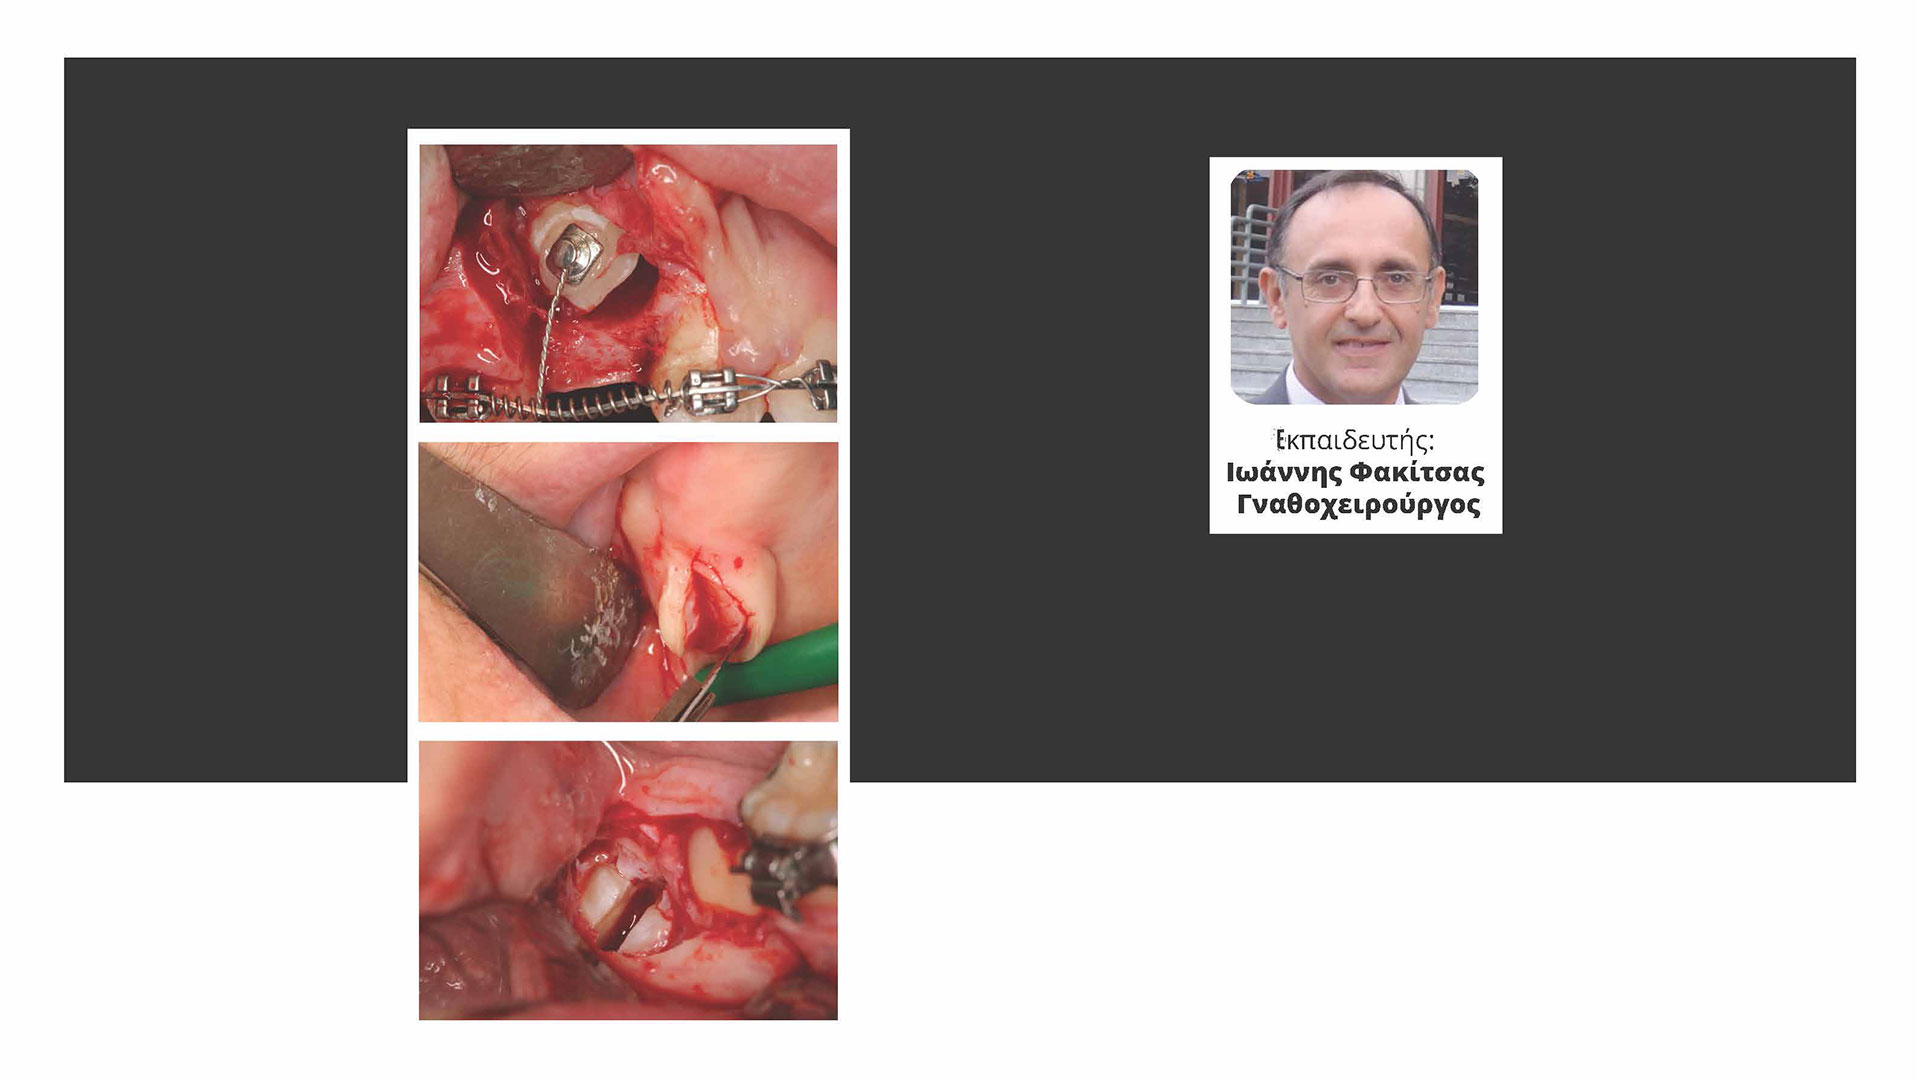

Το εκπαιδευτικό αυτό πρόγραμμα είναι η συνέχεια του προηγουμενου βασικού σεμιναριου Στοματικης Χειρουργικής αποτελούμενο από δύο μέρη συνδυάζει μια εμπεριστατωμένη εκπαίδευση με εις βάθος ανάλυση και ευκολοκατανοητα κλινικά περιστατικά και λεπτομερείς πρακτικές συμβουλές όσον αφορά τα εργαλεία-εξοπλισμό και χειρουργικά μυστικά και κόλπα στη Στοματική Χειρουργική.

Εχει σχεδιαστεί ετσι ώστε να διδάξει τεκμηριωμένη γνώση και σύγχρονη τακτική στη Στοματικη χειρουργική απο την πιο σύνθετη αφαίρεση εγκλειστου και εγκλειστων κυνοδόντων καθως και εκπαιδευση στη γναθορποσωπικη παθολογια και τεχνικες βιοψιας ιστων για διερυρνιση.

Στο δευτερο μέρος παρουσιαζεται το χειρουργικο σχεδιο θεραπειας στην αποκατάσταση του ασθενους με εμφυτευματα καθώς και τακτικες τοποθετισης εμφυτευματων σε διαφορες περιπτωσεις κλινικών προβληματων.

Ιωάννης Φακίτσας

Ο Ιωάννης Φακίτσας γεννήθηκε στη Νίκαια Αττικής το 1958.

Το 1981 απεφοίτησε από την Στρατιωτική Σχολή Αξιωματικών Σωμάτων και την Οδοντιατρική Σχολή του ΑΠΘ και κατετάγη στο Πολεμικό Ναυτικό οπου υπηρετησε ως το 2008 αποστρατευθείς με το βαθμό του Αρχιπλοιάρχου.

Την περίοδο 1985 εως 1989 εκπαιδεύτηκε στη Στοματική και Γναθοπροσωπική Χειρουργική στο Πανεπιστήμιο TUFTS της Βοστώνης των ΗΠΑ όπου έλαβε τον τίτλο της ειδικότητος την οποία αποκλειστικά υπηρετεί.